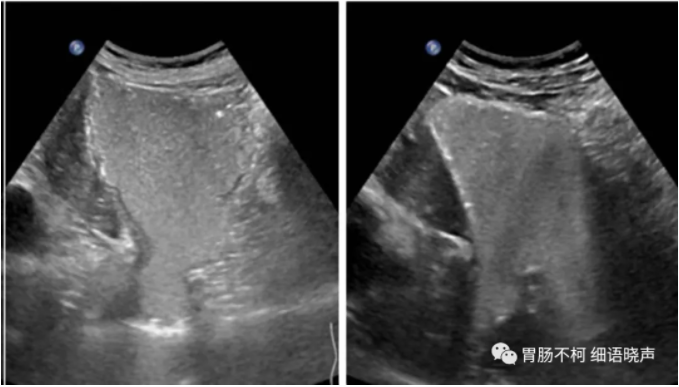

食管旁型:EGJ位于膈下,部分胃于食管腹段旁疝入膈上。

病例二,食管旁型食管裂孔疝:(图像来自于超声同仁提供,具体作者不详)